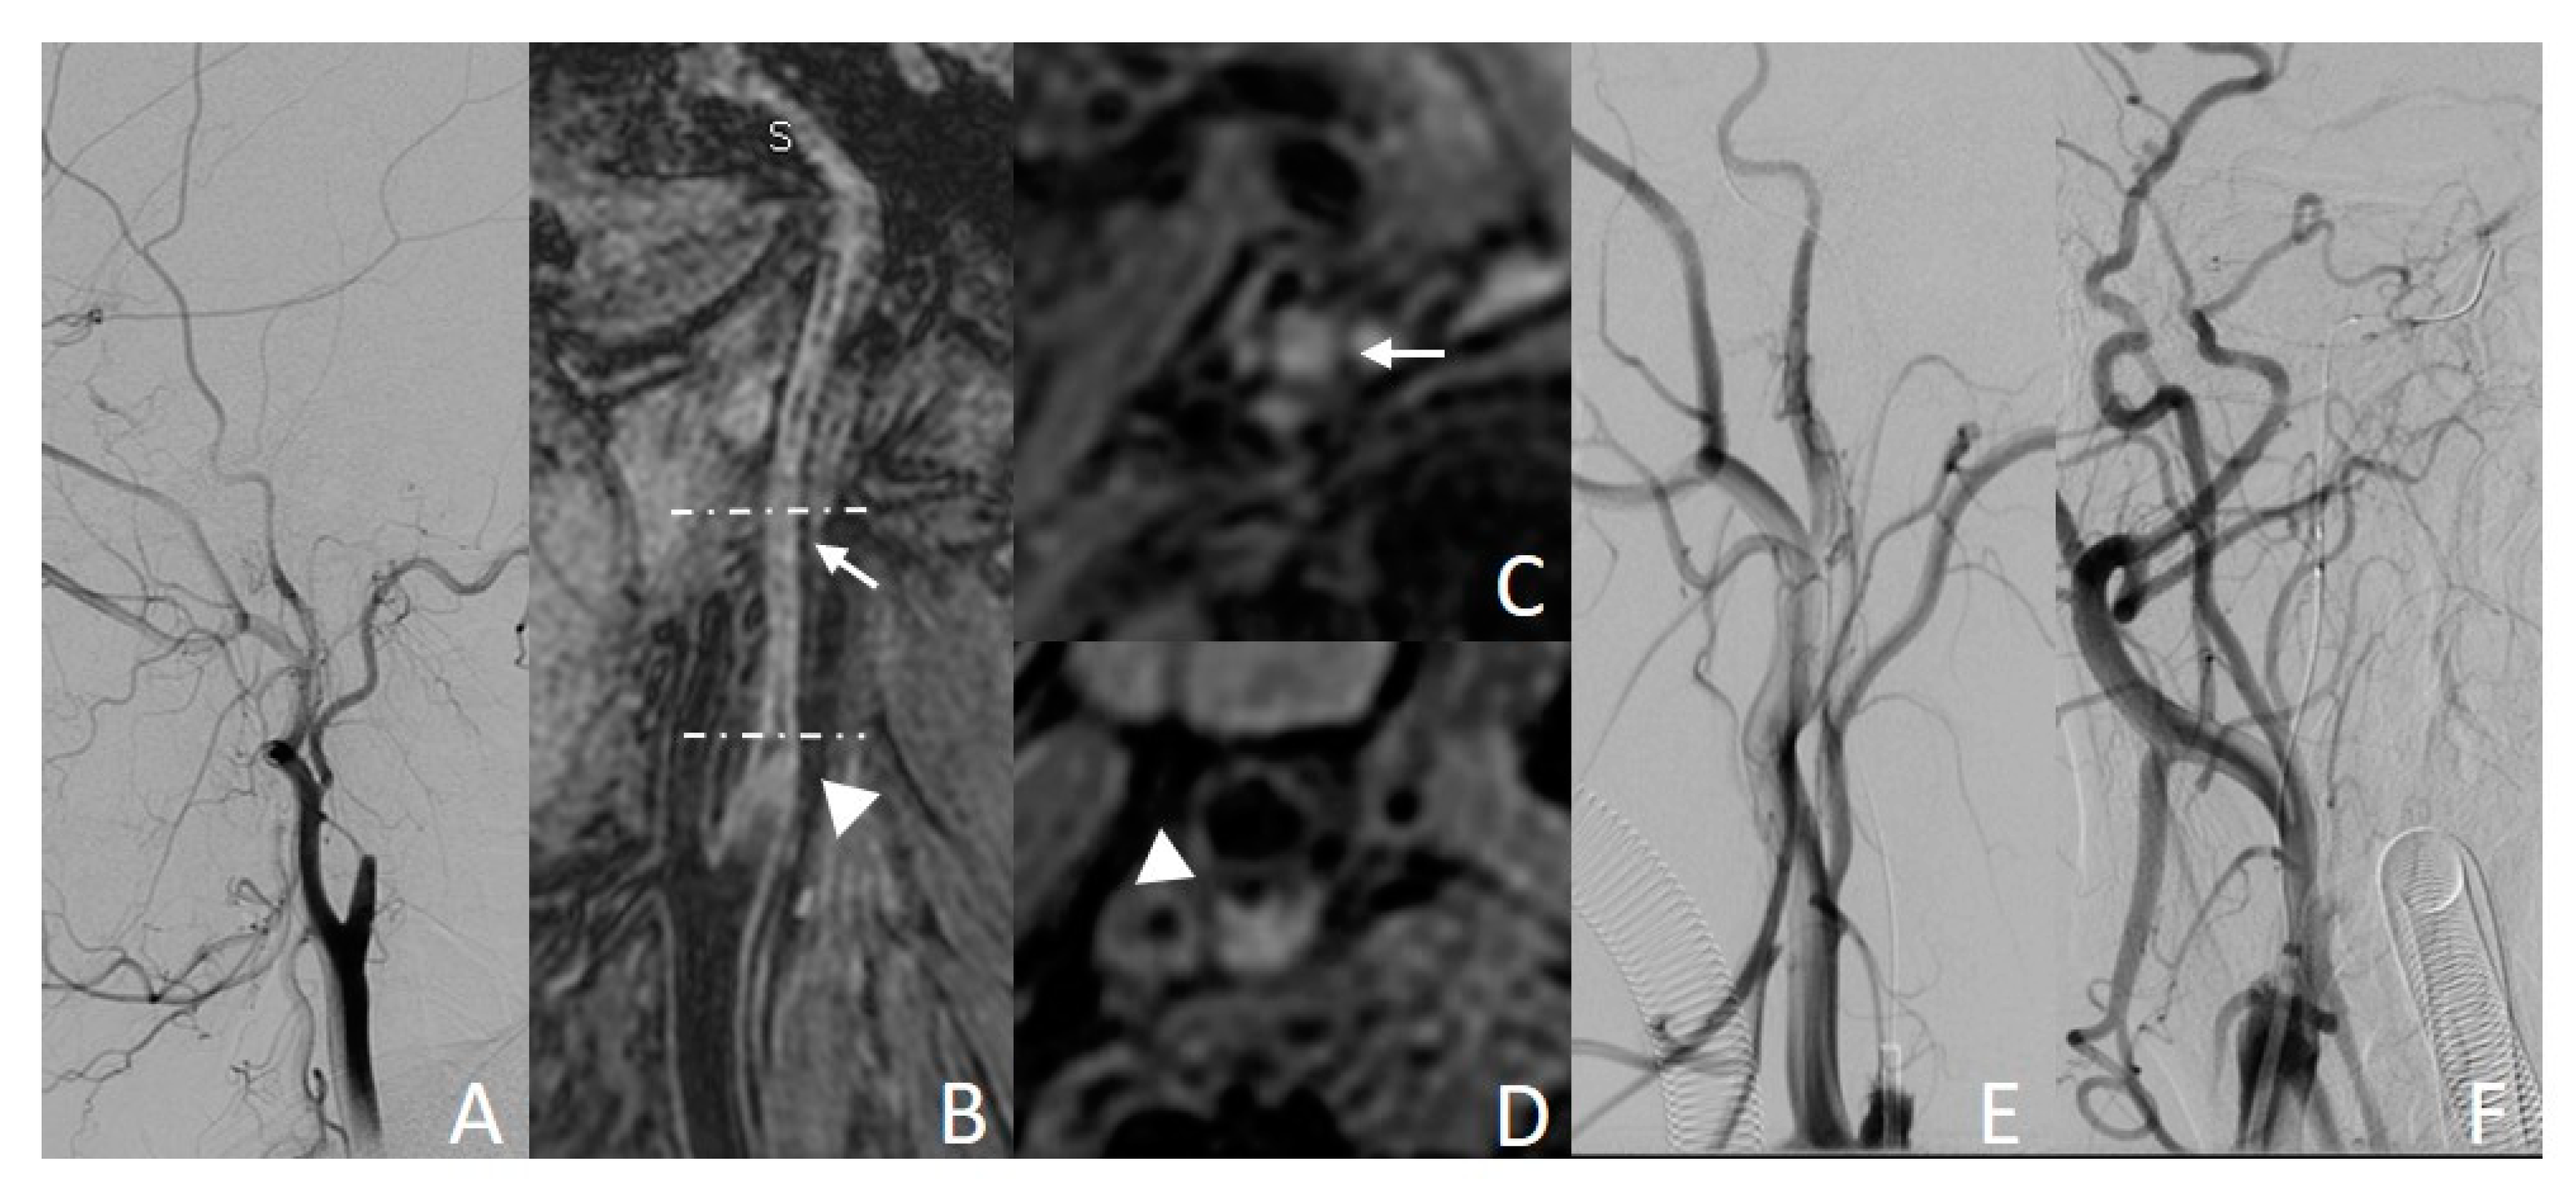

3.3.1. Example Case 1

A 62-year-old man was observed with left upper limb weakness 2 months before CICAO recanalization. Preoperative DSA showed right ICA occlusion (Figure 3A). The CICAO limited to the C1 segment was depicted by carotid 3D-MR-VWI. Severe hyperintense signal lesions can be observed (Figure 3B,D, arrow). Although mild eccentric calcification (Figure 3B,C, triangle) was found, the total MR CICAO score for this lesion was 4. The rate of successful guidewire crossing occlusion to the distal C3 segment was estimated to be very high, according to our MR CICAO score model, and as expected, this CICAO was endovascular recanalized successfully in the later intervention.

Figure 3.

Example case of successful endovascular recanalization. (A,E,F): DSA images; (B): MPR image of 3D MERGE; (C): axial image of 3D MERGE; (D): MPRAGE image. Hyperintense signal lesion ((B,D), arrow) and some signs of eccentric calcification ((B,C), triangle) can be observed on MR images.